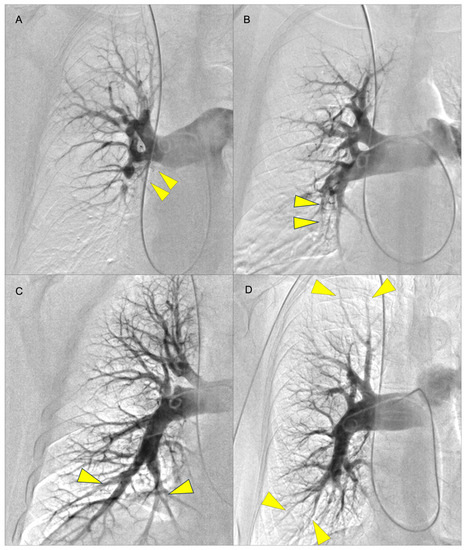

- Kawakami, T.; Ogawa, A.; Miyaji, K.; Mizoguchi, H.; Shimokawahara, H.; Naito, T.; Oka, T.; Yunoki, K.; Munemasa, M.; Matsubara, H. Novel Angiographic Classification of Each Vascular Lesion in Chronic Thromboembolic Pulmonary Hypertension Based on Selective Angiogram and Results of Balloon Pulmonary Angioplasty. Circ. Cardiovasc. Interv. 2016, 9, e003318. [Google Scholar] [CrossRef]

- Stępniewski, J.; Magoń, W.; Waligóra, M.; Jonas, K.; Bochenek, M.; Przybylski, R.; Podolec, P.; Kopeć, G. Hemodynamic effects of balloon pulmonary angioplasty for the treatment of total and subtotal pulmonary artery occlusions in inoperable chronic thromboembolic pulmonary hypertension. Int. J. Cardiol. 2022, 361, 71–76. [Google Scholar] [CrossRef]